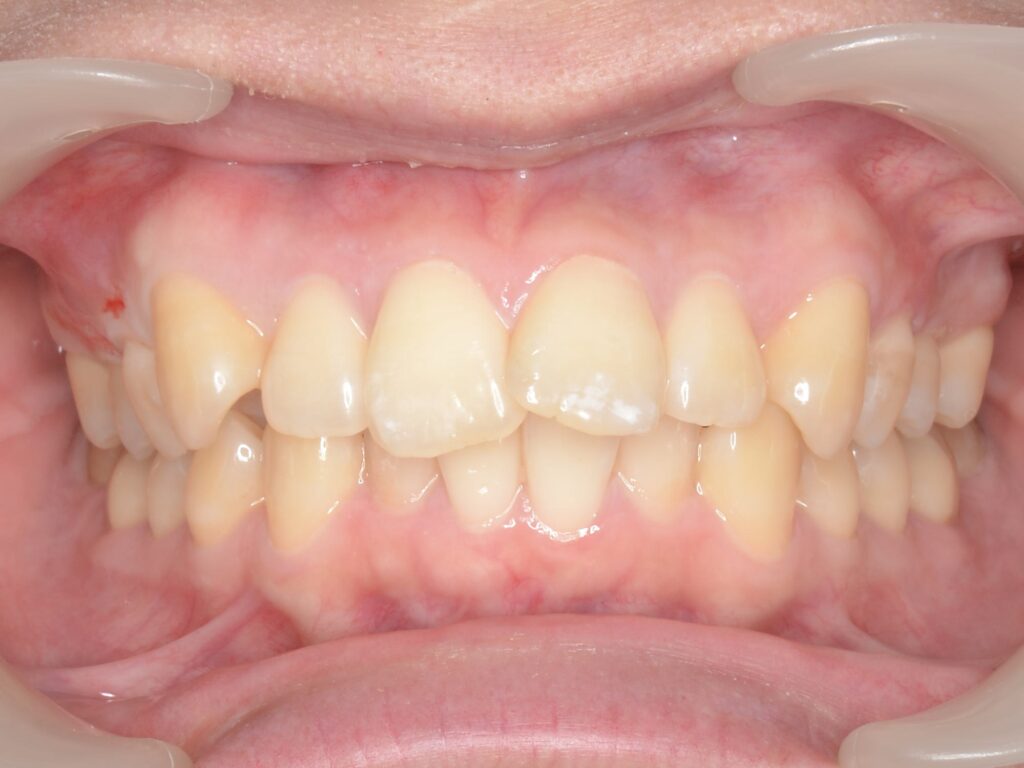

矯正治療の症例